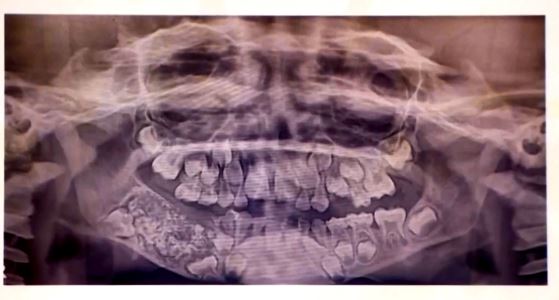

Όταν οι γιατροί έβγαλαν ακτινογραφία το στόμα του, βρήκαν έκπληκτοι έναν σάκο ενσωματωμένο στην κάτω γνάθο, γεμάτο με «μη φυσιολογικά δόντια», δήλωσε η Δρ. Πραθίμπα Ραμάνι, επικεφαλής της Στοματικής και Γναθοπροσωπικής Παθολογίας στο Πανεπιστημιακό Νοσοκομείο Saveetha Dental College.

«Υπήρχαν συνολικά 526 δόντια από 0,1 έως 15 χιλιοστά. Ακόμα και το μικρότερο δόντι είχε ρίζα και σμάλτο, που έδειχνε ότι επρόκειτο για δόντι», δήλωσε η δρ. Ραμάνι προσθέτοντας πως το αγόρι έπασχε από μια πολύ σπάνια κατάσταση που ονομάζεται σύνθετο οδόντωμα.